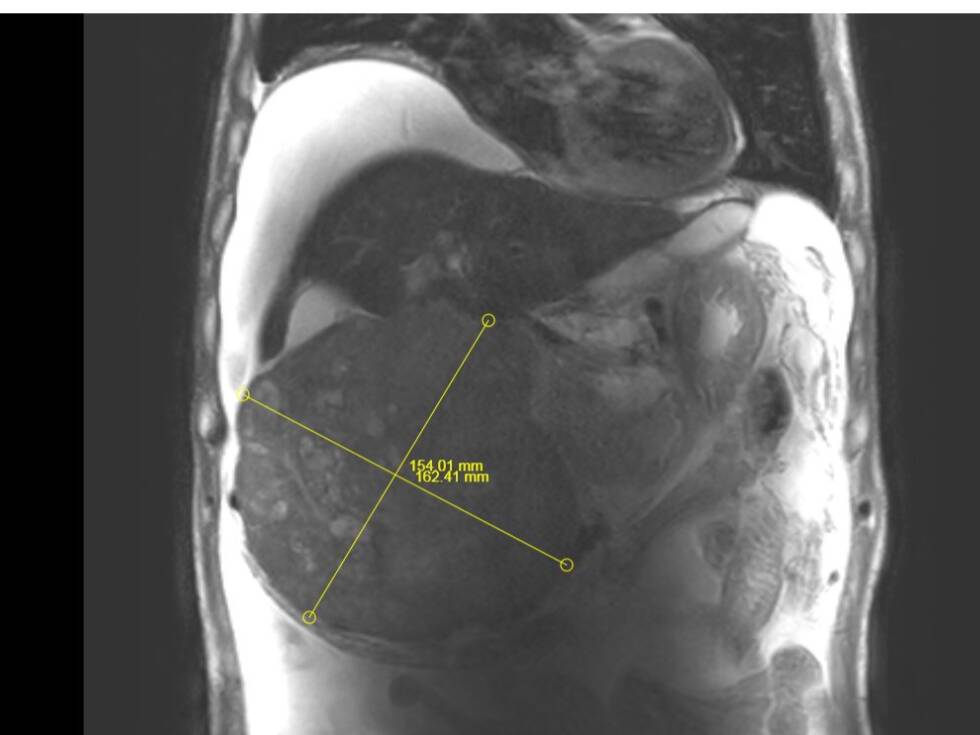

其中,成功为一名患者实施超大肝癌切除术,完整切除肿瘤大小达19cm×15cm,精准突破肝胆外科传统“手术禁区”,标志着普外二科在复杂肝胆肿瘤外科治疗领域迈上全新台阶。

此次切除的肿瘤体积巨大、血供丰富,与肝内重要血管、胆管粘连紧密,术中极易发生大出血、胆漏、肝功能衰竭等致命并发症。手术既要确保肿瘤完整根治、切缘干净,又要最大限度保留正常肝组织,难度与风险远超常规肝癌手术,对团队技术、经验与协作能力提出极高要求。

术前,科室联合影像、麻醉、重症监护、护理等多学科团队开展MDT会诊,全面评估肿瘤位置、大小、浸润范围及患者基础状况,精准规划切除路径与血管保护策略,反复推演手术流程,制定周密手术方案与应急预案,为手术成功筑牢坚实安全防线。